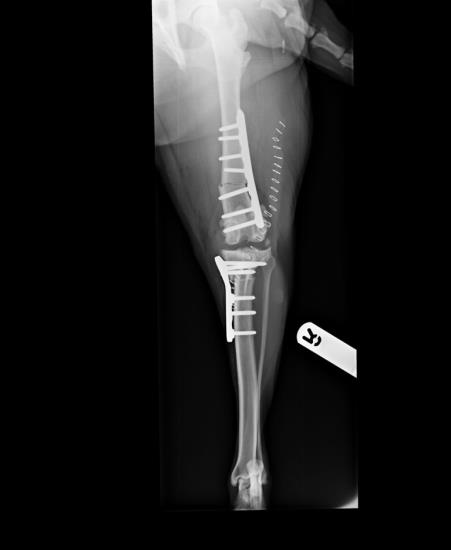

- Juvenile animals (Figure 3)

Figure 3. Treatment of cranial cruciate ligament avulsion in a 4-month-old Golden retriever using a cranial closing wedge ostectomy